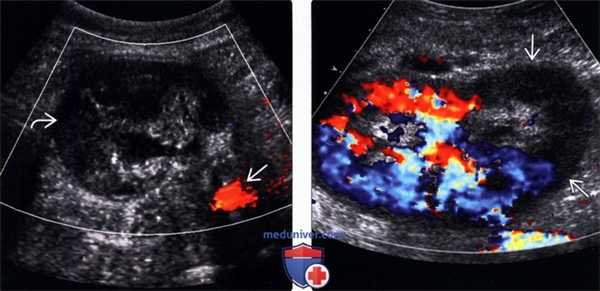

(Левый) На поперечном УЗ срезе с цветовой допплерографией тромбированного трансплантата почки после недавней операции визуализируется отекшая почка с отсутствием внутреннего цветового потока. Подвздошная артерия проходима.

(Правый) На продольном УЗ срезе с цветовой допплерографией визуализируется трансплантат почки с сегментарной ишемией нижнего полюса вследствие тромбоза добавочной почечной артерии. В нижней половине трансплантата отсутствует цветовой ток.